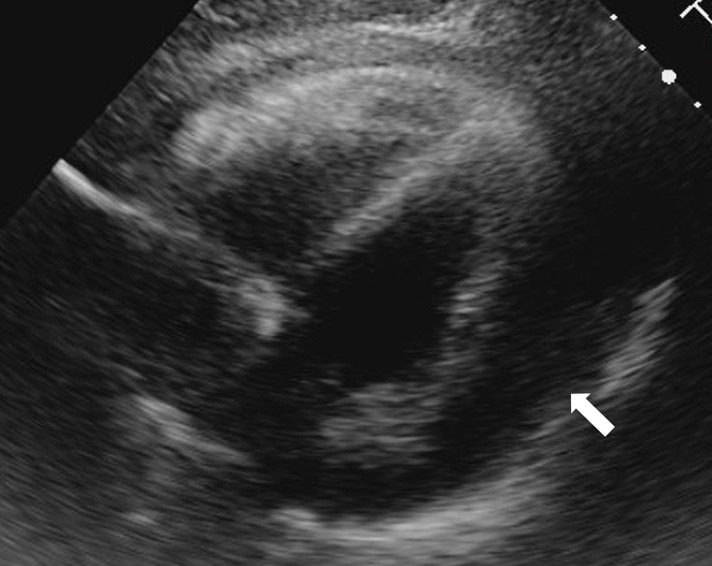

Case presentation: A 64-year-old woman, complaining of dyspnea for a month, was referred for a pulmonary artery tumor. Imaging studies confirmed an intraluminal tumor that obstructs the pulmonary artery trunk and extends to the right ventricular wall and interventricular septum, suspecting a malignancy. During preoperative workups, she developed acute hemodynamic and respiratory deterioration due to pulmonary embolization, so emergency surgery was planned on a salvage basis. The tumor originated from the pulmonary artery intima just distal to the pulmonary valve, obstructed the pulmonary artery trunk, and extensively involved the left main coronary artery and the interventricular septum, where complete resection of the tumor was not achieved. Reconstruction of the pulmonary valve, the right ventricular outflow tract (RVOT), and bilateral pulmonary arteries were performed using a composite of a prosthetic valve and vascular grafts. The patient's postoperative course was uneventful, and she was discharged home asymptomatic. Pathological diagnosis of the operative specimen confirmed pulmonary intimal sarcoma. After 4 months of postoperative chemotherapy, tumor progression was confirmed. The patient passed away at home 8 months after surgery.